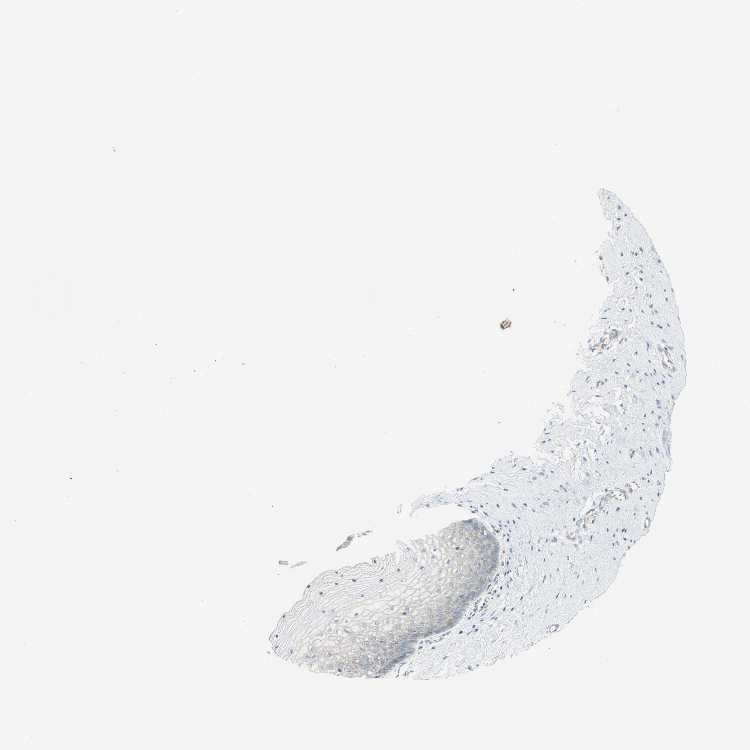

VAGINA - Antibody stainingi

Antibody staining in the annotated cell types in the current human tissue is reported as not detected, low, medium, or high, based on conventional immunohistochemistry profiling in selected tissues. This score is based on the combination of the staining intensity and fraction of stained cells.

Each image is clickable and will lead to virtual microscopy that enables deeper exploration of all samples and also displays staining intensity scores, fraction scores and subcellular localization as well as patient and tissue information for each sample.

Antibody CAB006254

Squamous epithelial cells Low